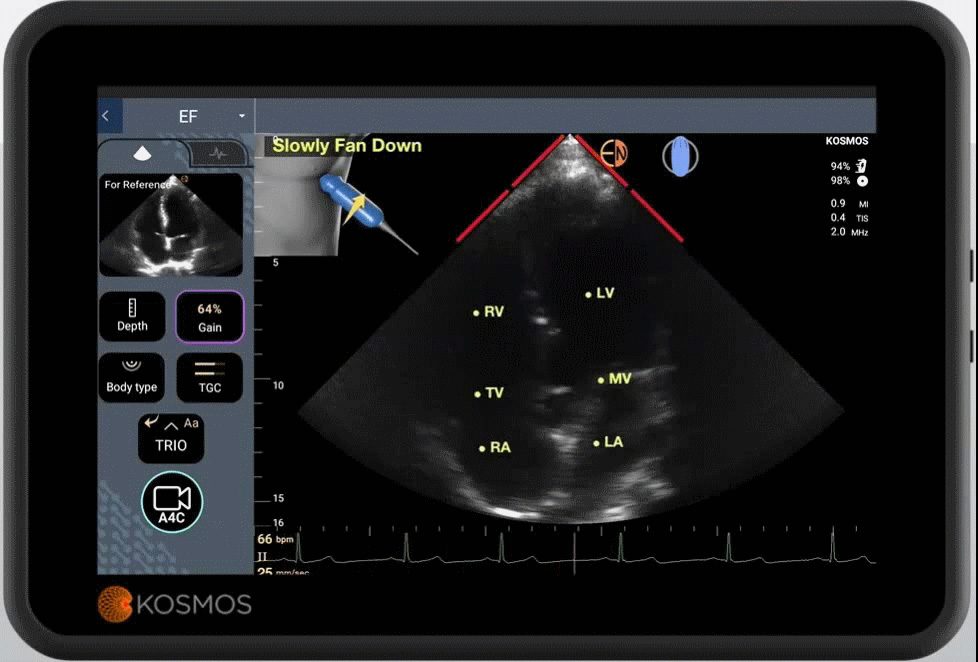

公司公开资料显示 , Us2.ai 创立于2017年 , 使用人工智能开发超声心动图软件和数字工具 , 其开发的第一款软件是新加坡科学、技术和研究机构支持的11个国家心血管研究平台的第一个衍生产品 , 提供在线解决方案以简化回波分析和心脏超声结果的访问 。 Us2.ai 开发的一款人工智能超声心动图软件 , 利用机器学习技术为市场提供一套解决方案 , 该软件可以自动处理超声心动图 , 并给出分析报告 , 通过与便携式回声设备结合 , 它能够在两分钟内为患者提供完整和准确的心脏测量结果 , 从而实现病患及家属在不借助医生帮助的情况下 , 自主阅读超声心动图 , 达到速度更快且花费更低的效果 。 此外 , Us2.ai 的软件工具还可以帮助医生提高制定临床决策的效率及更方便地开展心血管疾病方面的临床试验 。

Us2.ai 的这套软件工作流程已获批专利 , 并在全球多个真实就诊环境中使用后证实有效 。